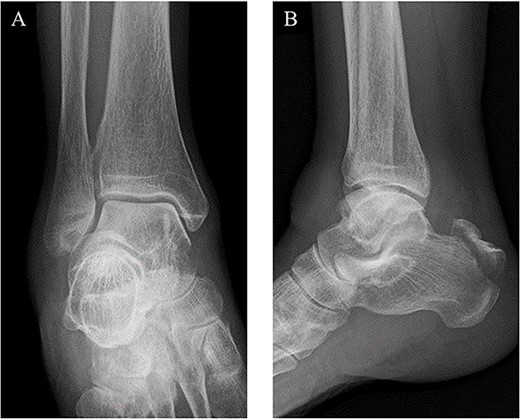

A 78-year-old woman complained of right heel pain when tripping during walking and visited to our hospital. She had medical histories such as arrhythmia, hypertension and hyperlipidemia. Physical examination revealed swelling, subcutaneous bleeding and tenderness on the posterior aspect of her heel and Thompson test was positive. Plain radiographs of the right ankle showed an avulsion fracture of the calcaneal tuberosity (Fig. 1). Non-contrast computed tomography (CT) demonstrated that the bone fragment was displaced. Based on medical histories, physical examination and image findings, we diagnosed an avulsion fracture of the calcaneal tuberosity and applied surgical treatment for the patient.

Plain radiographs of the right ankle showed no abnormal findings in (A) an anteroposterior view, but an avulsion fracture of the calcaneal tuberosity (B) a lateral view.